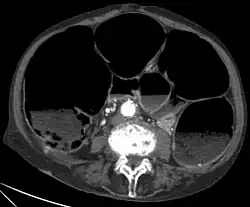

• CT-Scan showing a Cross-section of the abdomen of an elderly lady with an IPO.

The symptoms of IPO are nonspecific. It is not unusual for patients to present repeatedly and to undergo numerous tests.[4] Mechanical causes of intestinal obstruction must be excluded to reach a diagnosis of pseudo-obstruction. Attempts must also be made to determine whether the IPO is the result of a primary or secondary condition.[15] A diagnostic work-up may include:[14]